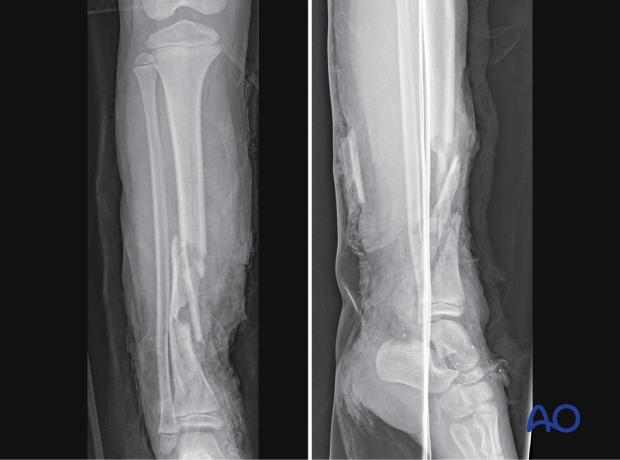

- Simple and multifragmentary fractures of the tibial shaft

This includes detailed procedures on elastic stable intramedullary nailing (ESIN), external fixation, and plate fixation, in addition to nonoperative management with casting and splinting.